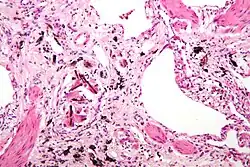

De stoflongziekte, ook bekend als mijnwerkers-pneumoconiose, ontstaat door langdurige blootstelling aan kolengruis. Dit stof kan niet worden afgebroken of verwijderd door het lichaam, waardoor het zich ophoopt in de longen en ontstekingen en littekens veroorzaakt (bindweefselvermeerdering). Het meest voorkomende symptoom is kortademigheid. Daarnaast kan de ziekte leiden tot emfyseem en hartfalen.